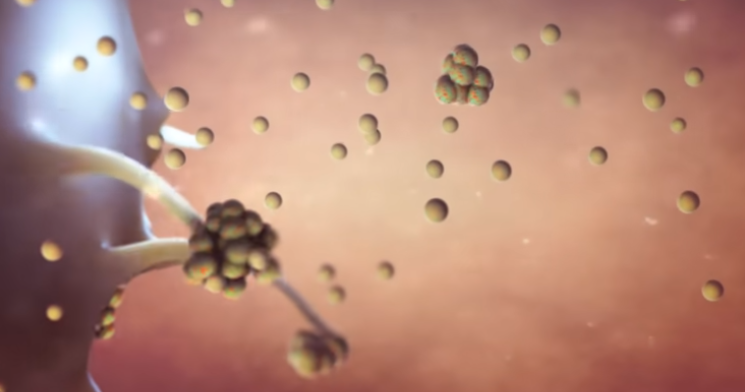

其中,在冠状突起中最重要的一种蛋白叫做刺突糖蛋白(蓝色),这种蛋白可以识别人体细胞的表面ACE2蛋白(黄色)。举个例子,ACE2蛋白像一把锁,一般只有配对的钥匙才能打开它进入细胞内部。一颗合格的病毒会利用自己的技能合成出一把刺突糖蛋白仿制钥匙,堂而皇之的侵入细胞。这个过程就像这样:

如果识别成功,那么接下来在蛋白质外壳的协助下,病毒会使用细胞融合技能进入人体细胞。

整个过程就像病毒利用自己仿制的钥匙开启了人体细胞的大门。